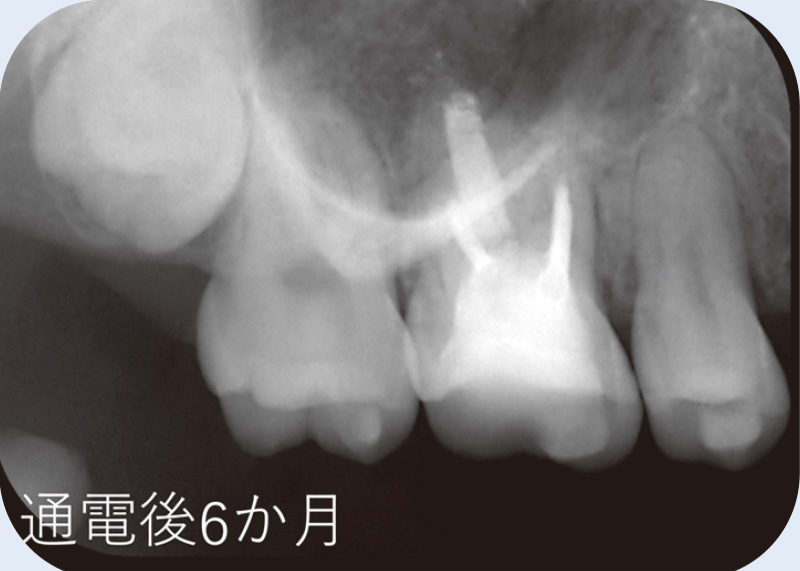

![[写真] 通電後6か月](/academic/dentalmagazine/wp-content/uploads/sites/2/2025/11/195-3_photo12.jpg)